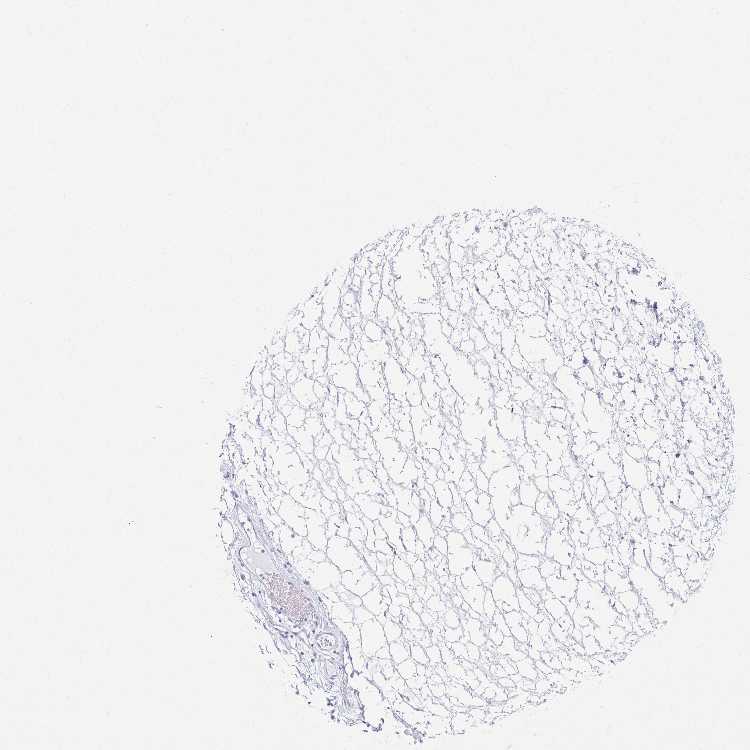

PRKCG